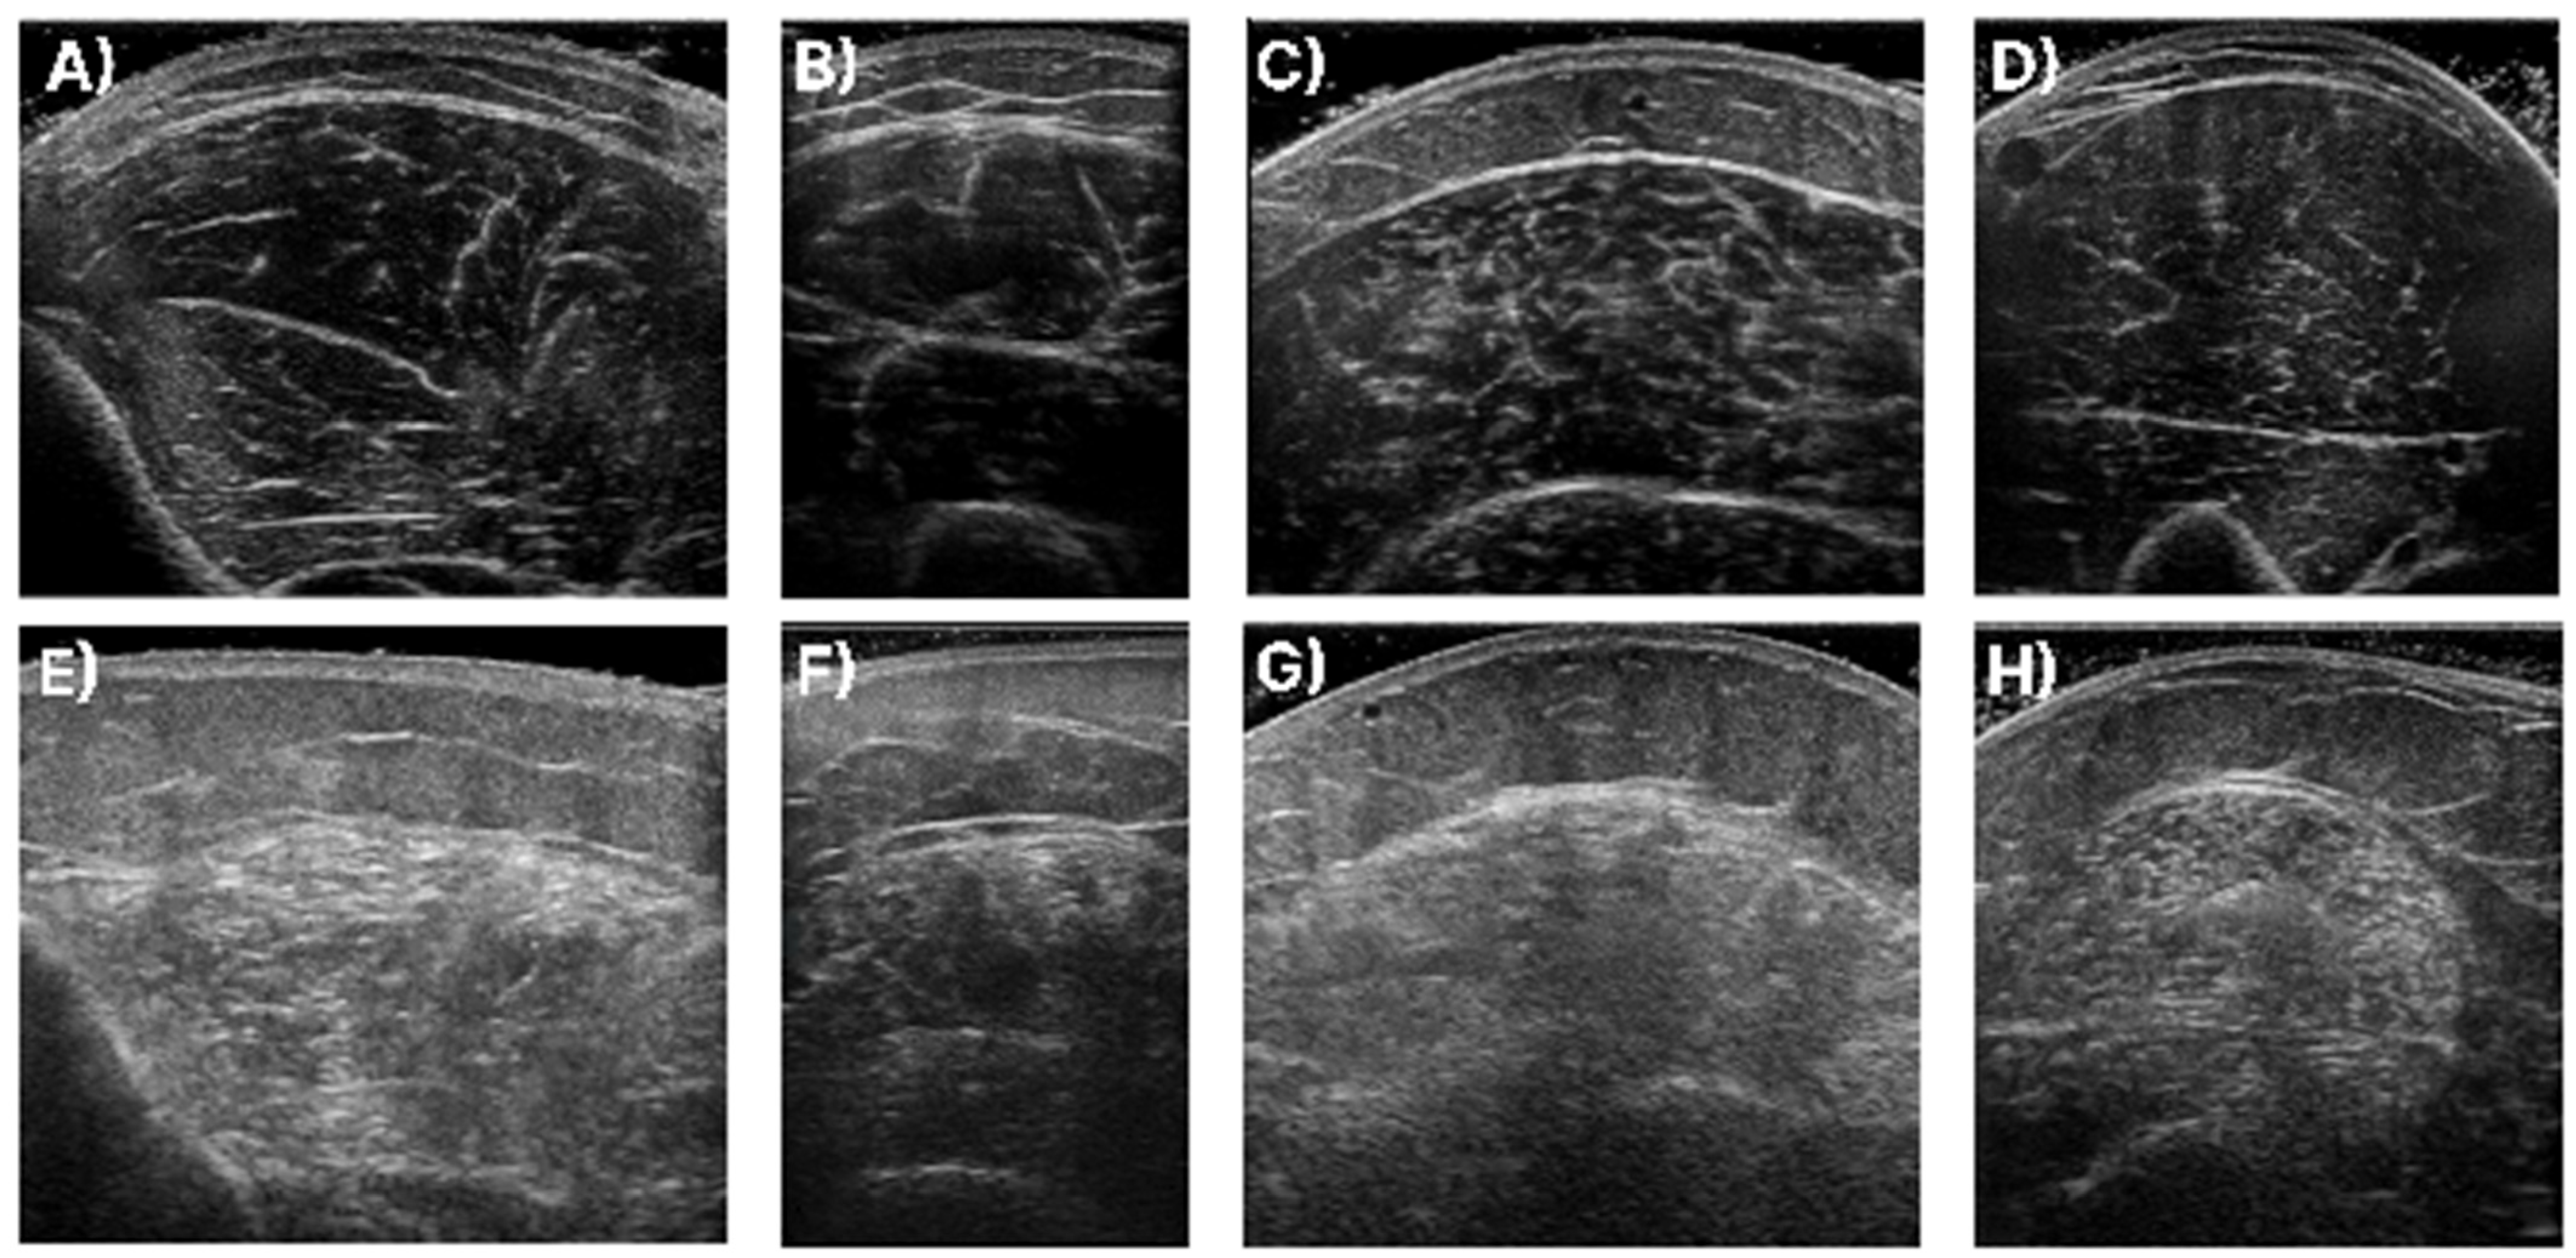

In Figure 1, samples of the studied muscles are presented for normal and high echogenicity images. It is observable in these images that the muscle aponeuroses, especially in the high echogenicity images, are hard to distinguish from the other muscle tissue, making the accurate localisation of the CSA more challenging.

Figure 1. Sample of ultrasound recordings with normal and high echogenicity. (A,E) shows images from the T.A., (B,F) shows images from the R.F., (C,G) shows images extracted from the GCM, and finally, (D,H) are images of the B.B.